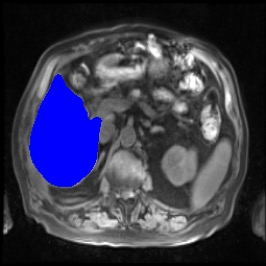

Integrating high-level semantically correlated contents and low-level anatomical features is of central importance in medical image segmentation. Towards this end, recent deep learning-based medical segmentation methods have shown great promise in better modeling such information. However, convolution operators for medical segmentation typically operate on regular grids, which inherently blur the high-frequency regions, i.e., boundary regions. In this work, we propose MORSE, a generic implicit neural rendering framework designed at an anatomical level to assist learning in medical image segmentation. Our method is motivated by the fact that implicit neural representation has been shown to be more effective in fitting complex signals and solving computer graphics problems than discrete grid-based representation. The core of our approach is to formulate medical image segmentation as a rendering problem in an end-to-end manner. Specifically, we continuously align the coarse segmentation prediction with the ambiguous coordinate-based point representations and aggregate these features to adaptively refine the boundary region. To parallelly optimize multi-scale pixel-level features, we leverage the idea from Mixture-of-Expert (MoE) to design and train our MORSE with a stochastic gating mechanism. Our experiments demonstrate that MORSE can work well with different medical segmentation backbones, consistently achieving competitive performance improvements in both 2D and 3D supervised medical segmentation methods. We also theoretically analyze the superiority of MORSE.